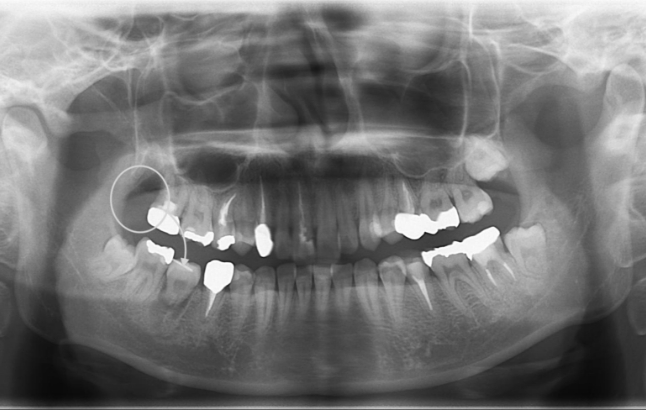

歯牙移植による右下部位の治療例

- 年代、性別 20代・女性

- 来院動機 他院で右下の歯を抜き、インプラントを勧められたが、歯牙移植ができないか相談したいと来院されました。

- 治療内容 右下の残せない歯を抜歯し、ご自身の不要な親知らずを取り出して、右下の抜歯部に移植しました。

- 治療期間 約2週間

- 治療費用 176,000円(税込)

以下の写真の患者様は、移植した歯の歯根根の成長がまだ終わっていなかったため、歯を削ったり神経を取ったりすることなく、移植から11年経った現在も、そのままの状態で自分の歯として元気に機能しています。